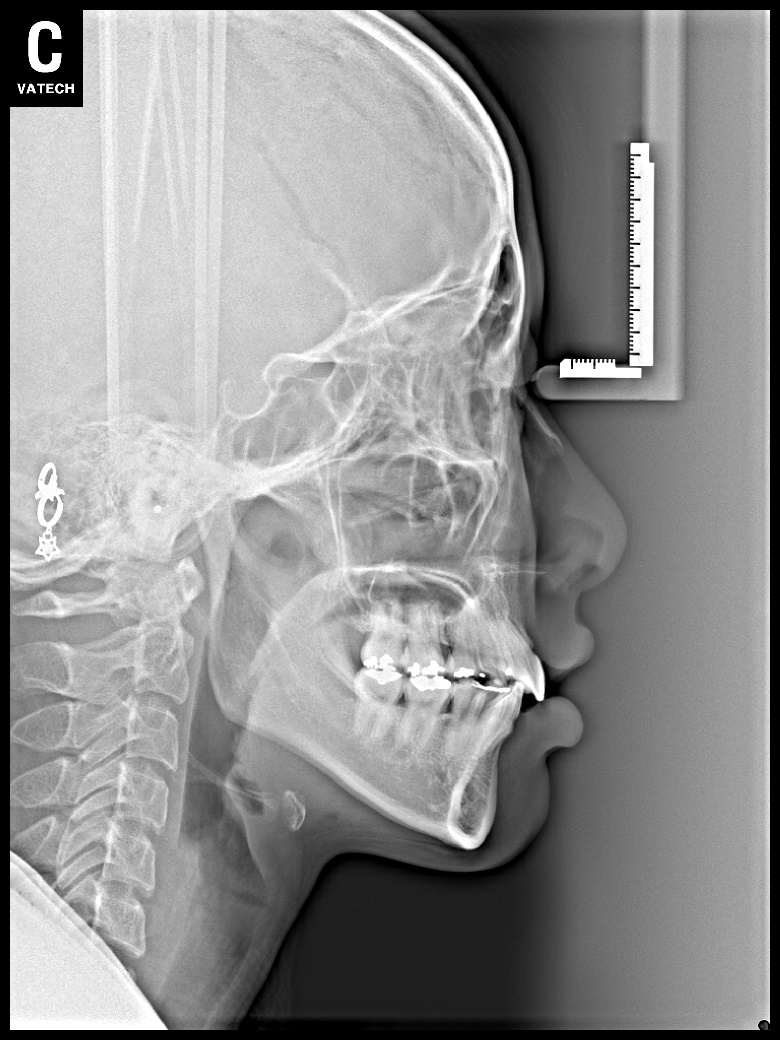

치료 후 사진입니다.